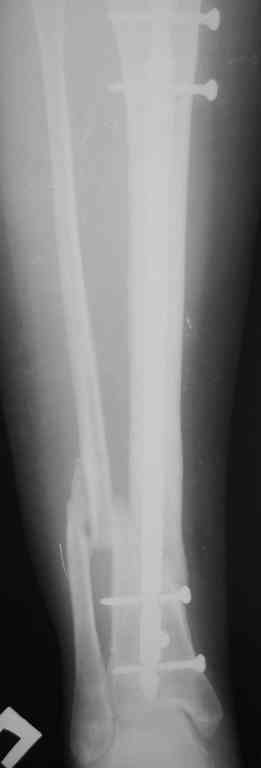

Re: Ложный сустав голени перелом штифта

послал В. Машталов 23 Октябрь 2007, 12:09

Прилагаются.